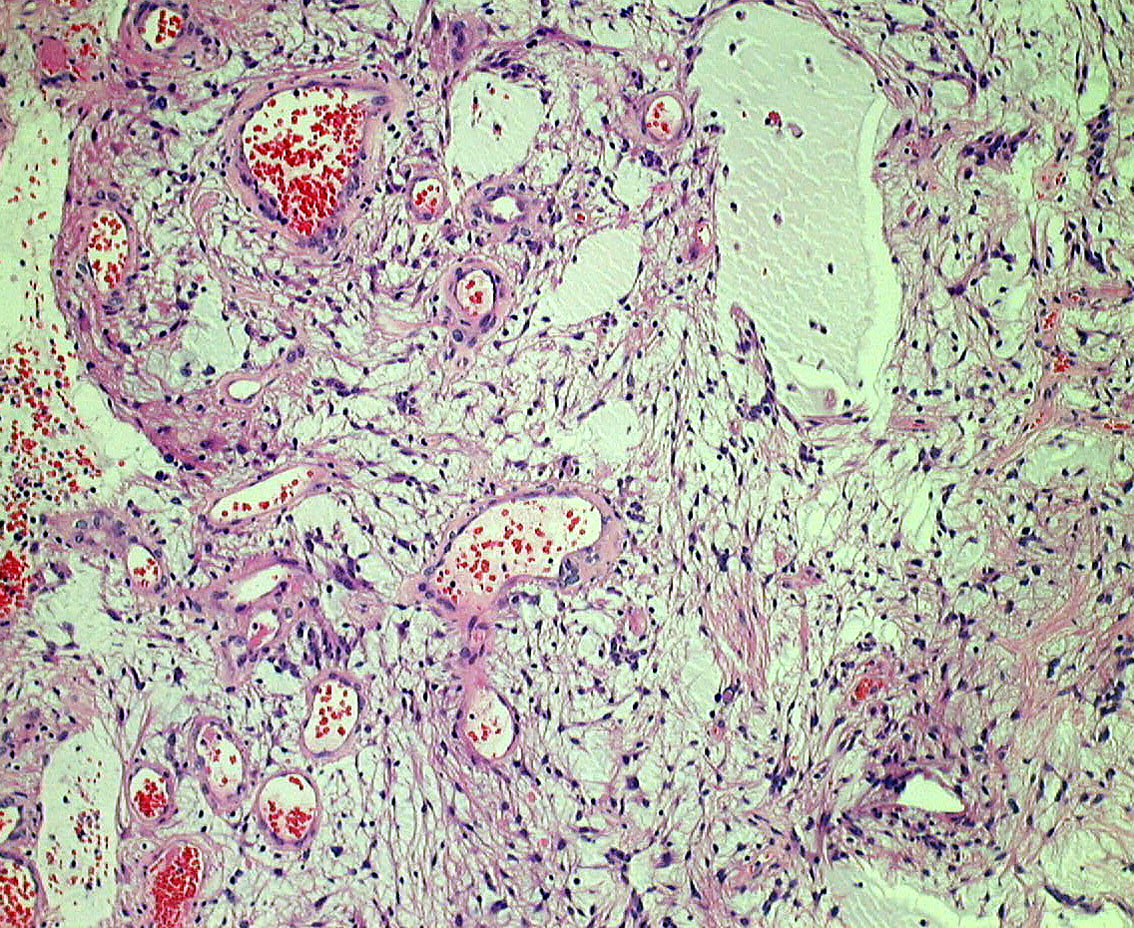

生後6ヶ月の視神経交叉腫瘍です。左では,monomorphous bipolar cellsとmucoid matrixが豊富に見られます。右では細い血管の周囲に腫瘍細胞が集簇するangiocentric patternが特徴的です。粘液性分が多くドロドロした腫瘍です。

3歳児例でのangiocentric patternで,乳児例より多少コンパクトになってきます。毛様粘液性星細胞腫においてもGFAP(右側)は強陽性です。